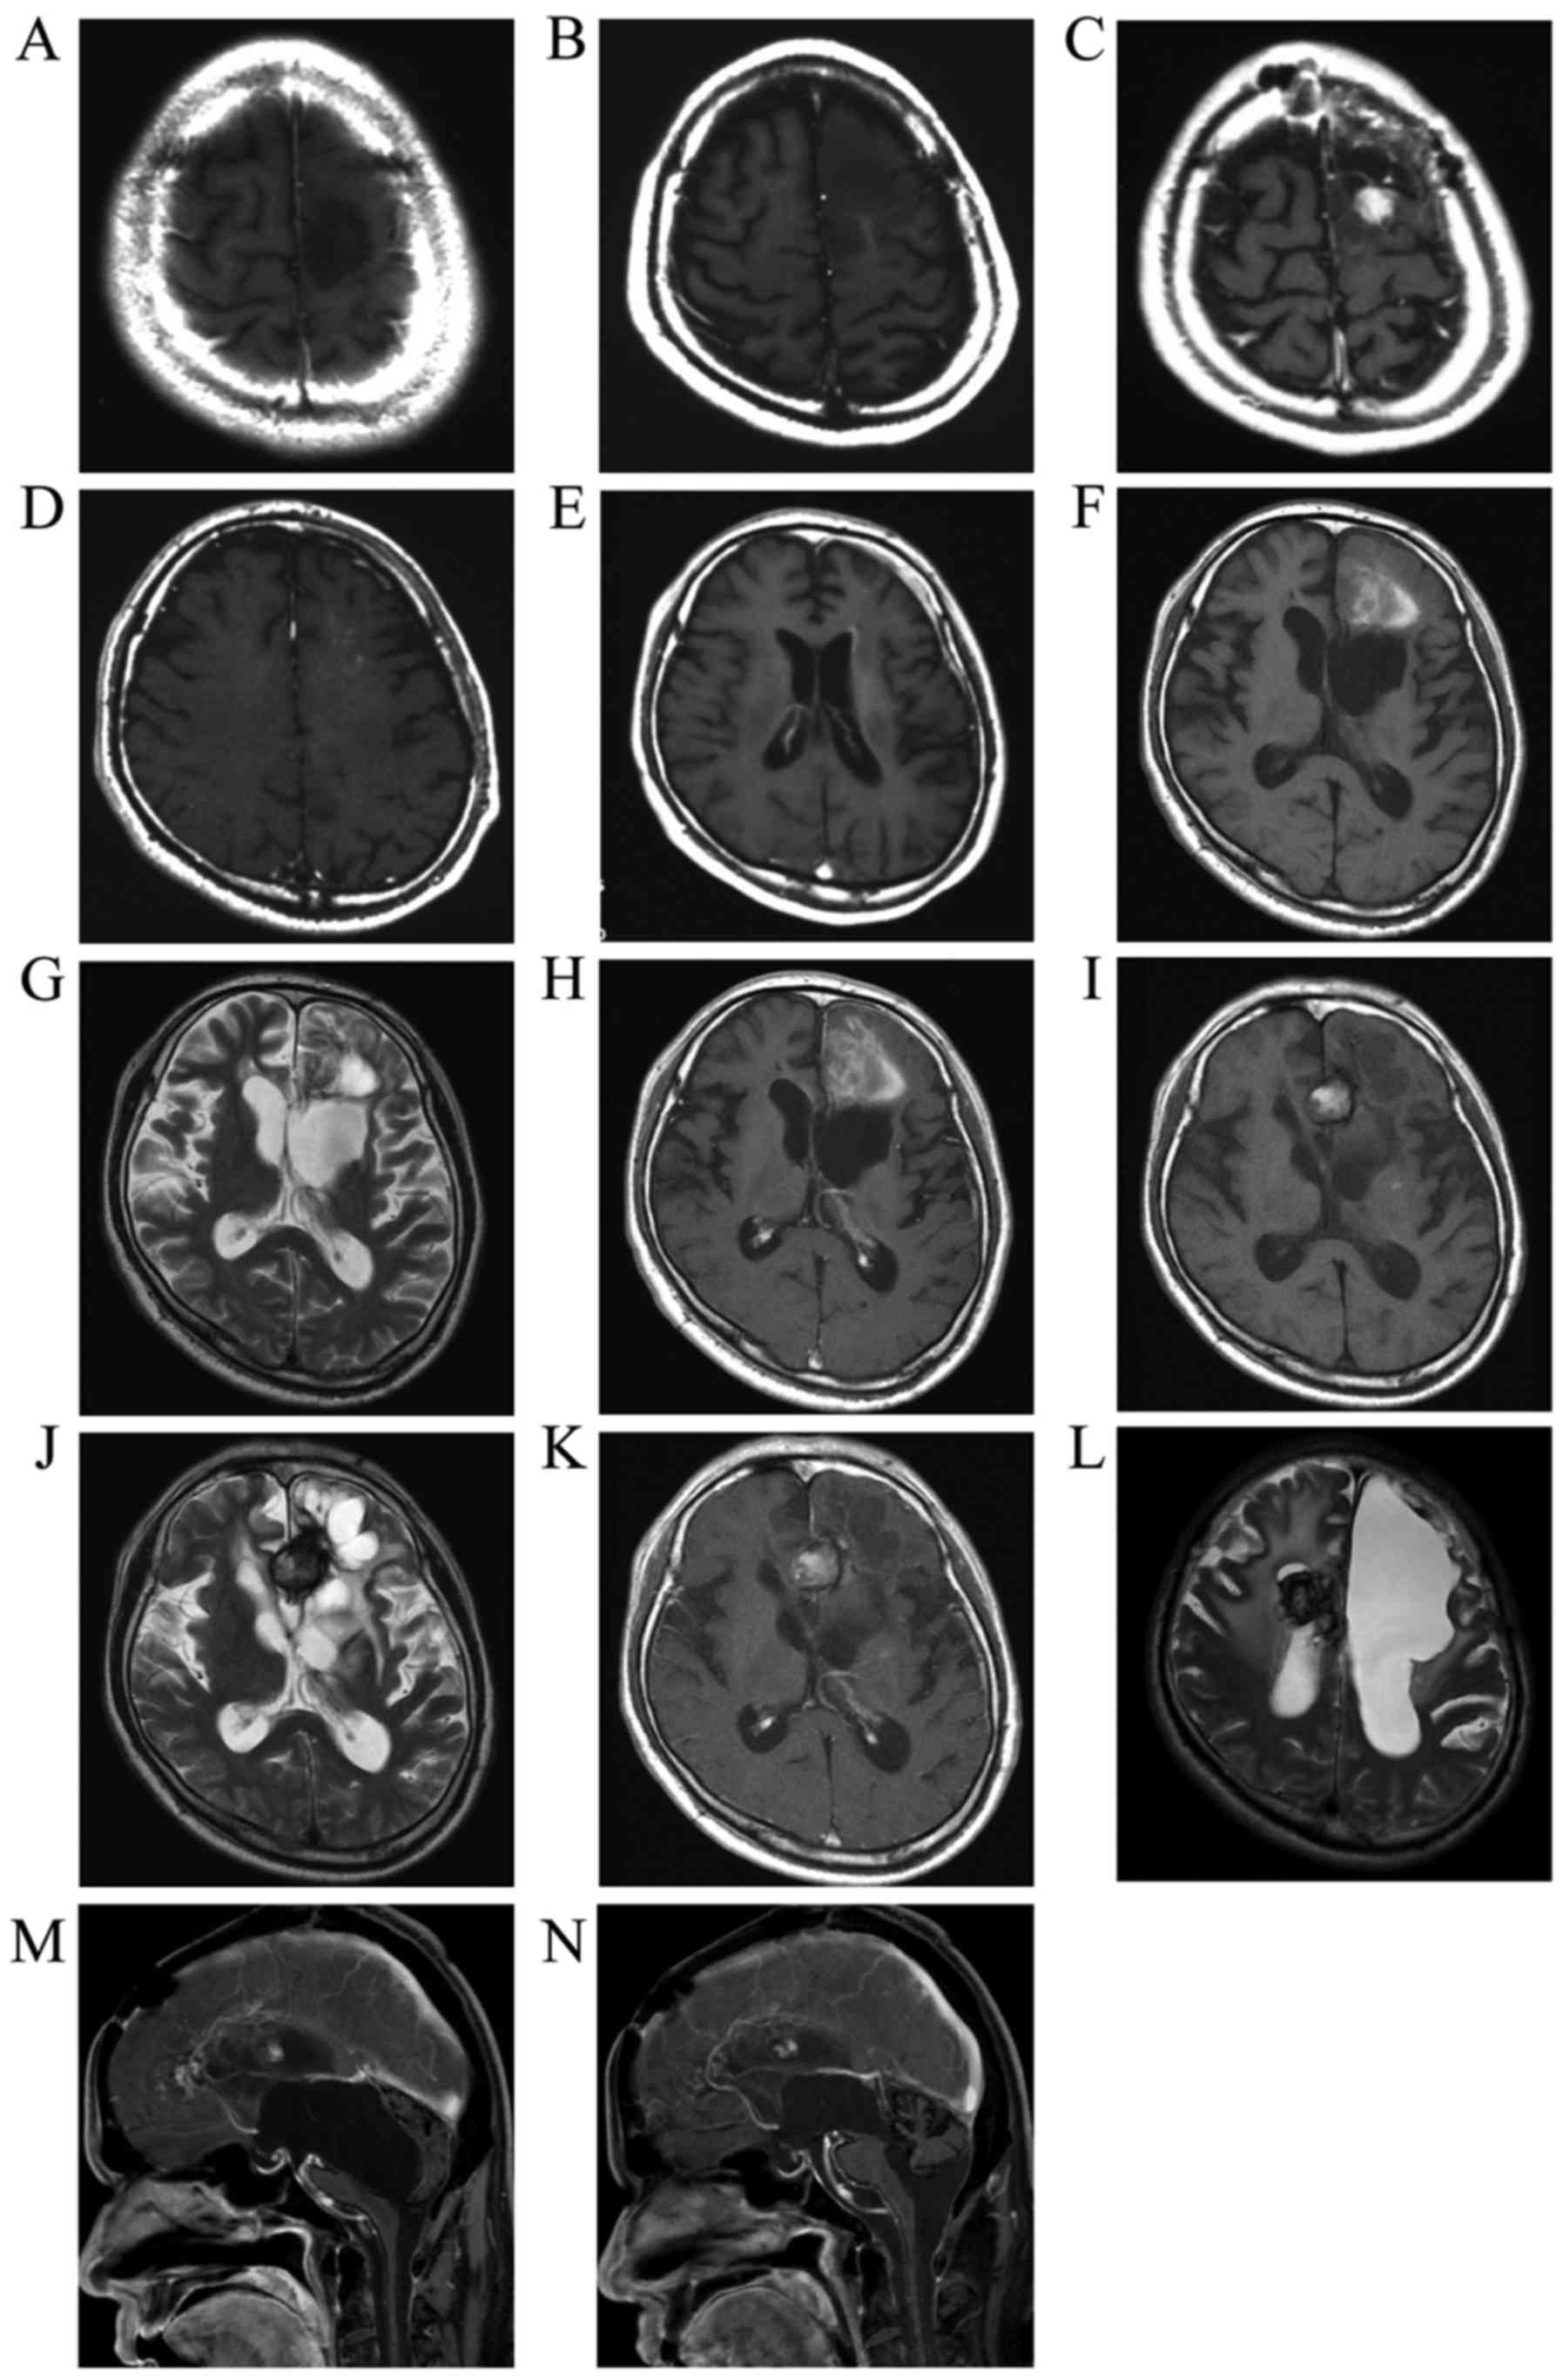

Figure 1.

(A) Initial T1-weighted image following gadolinium (Gd) administration (T1Gd). (B) Tumor recurrence prior to the second surgery (T1Gd). (C) Tumor recurrence exhibiting contrast enhancement following Gd administration prior to the third surgery. (D) A new lesion detected in the deep left frontal lobe (T1Gd). (E) Invasion of the tumor extending to the left lateral ventricle. (F) Plain T1-weighted image, (G) T2-weighted image and (H) T1Gd showing bleeding in the tumor of the left frontal lobe. The intratumoral bleeding progressed to a demarcated hematoma as seen on (I) plain T1, (J) T2 and (K) T1Gd images. (L) The same type of demarcated hematoma (hemangioma) occurred in the right hemisphere. (M) Hydrocephalus prior to endoscopic surgery, with a cyst caused by obstruction of the aqueduct protruding into the fourth ventricle. (N) Following endoscopic surgery, the aqueduct was recanalized and the compression of the brain stem was relieved.

A 35-year-old man who experienced a convulsive episode originating in the right side was referred to Kagoshima University Hospital (Kagoshima, Japan). Magnetic resonance imaging (MRI) indicated the presence of a tumor in the left frontal lobe. The hypointense tumor on T1-weighted images did not exhibit contrast enhancement following Gd contrast medium administration (Fig. 1A). The patient underwent the first tumor removal surgery in February, 1999, and the histological diagnosis was anaplastic astrocytoma (Fig. 2, row 1). The retrospective analysis for 1p/19q status by fluorescence in situ hybridization revealed no co-deletion. A second surgery was performed 2 years and 5 months after the first surgery due to tumor recurrence in the anterior wall of the removal cavity (Fig. 1B) and the histological diagnosis was diffuse astrocytoma (Fig. 2, row 2). At 3 years and 3 months after the first surgery, tumor recurrence was detected as a mass displaying contrast enhancement following Gd administration (Fig. 1C) and the histological diagnosis of the specimens from the third surgery was anaplastic astrocytoma (Fig. 2, row 3). The MIB-1 index of the specimen was ~30%. The patient subsequently underwent radiotherapy (40 Gy of extended-field irradiation and 20 Gy of local irradiation) and chemotherapy with nimustine hydrochloride (ACNU) 100 mg on day 1 and vincristine 2 mg on days 1, 21 and 42, every 6–8 weeks. After 2 cycles of chemotherapy, a new lesion appeared in the deep frontal lobe (Fig. 1D). The patient underwent a fourth surgery 3 years and 8 months after the first surgery (Fig. 2, row 4). Despite continuing chemotherapy and additional CyberKnife treatment, an invasive tumor extended into the wall of the left lateral ventricle (Fig. 1E) and the patient underwent a fifth tumor removal surgery 4 years and 6 months after the first surgery (Fig. 2, row 5).

At 5 years and 3 months after the first surgery, ACNU was replaced with TMZ for 5 days every 4 weeks, as tumor growth and invasion were not controlled by ACNU treatment. The tumor continued to grow, extending to the right frontal lobe through the corpus callosum after 6 cycles of TMZ treatment; however, the tumor growth decelerated. By the 22nd cycle of TMZ treatment, tumor growth had been arrested. TMZ treatment was continued according to the wishes of the patient and his family. At 8 years and 8 months after the first surgery, the 41st cycle of TZM treatment was administered and tumor progression was suppressed. This patient's long-term, 41-cycle TZM treatment was previously reported in the Japanese language CP Neurosurgery journal, as case 1 in an article reporting long-term TMZ treatment in two patients with high-grade glioma (3). Prior to the 42nd TZM treatment, hemorrhage occurred in the residual tumor that displayed contrast enhancement following Gd administration in the left frontal lobe (Fig. 1F-H). The hemorrhagic lesion was converted to a circumscribed hematoma and the size gradually increased (Fig. 1I-K). The patient underwent a sixth surgery to remove the hemorrhagic lesion 11 years and 3 months after the initial surgery. The circumscribed hematoma (Fig. 3A and B) and surrounding tissue (Fig. 2, row 6) were removed after the 69th TMZ treatment and TMZ treatment was continued after this surgery. Additional new lesions were detected in the right frontal lobe. According to the continuous MRI observation, the T2 hypointense mass in the right frontal lobe was diagnosed as a hemangioma, suspected to have developed post-radiation therapy (Fig. 1L). Several new hemangiomas appeared, but no further lesions indicating glioma recurrence. Eleven years and 7 months after the first surgery, the patient was admitted to another hospital due to deterioration of daily activities under continuing TMZ treatment; he underwent neuroendoscopic surgery 13 years and 8 months after the first surgery to treat the hydrocephalus (Fig. 1M) caused by continuous bleeding into the ventricles from the hemangiomas. During the surgery, a cloudy fluid was observed, with precipitation of the hematoma over the aqueduct. Short-term recovery was achieved by relieving the obstruction of the aqueduct and performing a third ventriculostomy by endoscopic surgery (Fig. 1N), but the patient succumbed to respiratory failure caused by severe hydrocephalus with perpetual hemorrhage from the hemangiomas (14 years and 9 months from the first surgery). An autopsy was performed and the brain tissue was carefully examined.